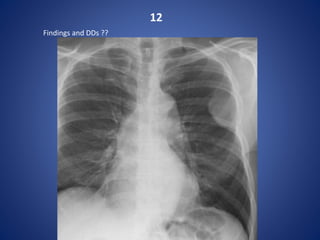

12

Findings and DDs ??

A pleural based malignant mass with overlying rib destruction - Plasmacytoma

DDs:

pleural fibroma

Mesothelioma

Pleural mets